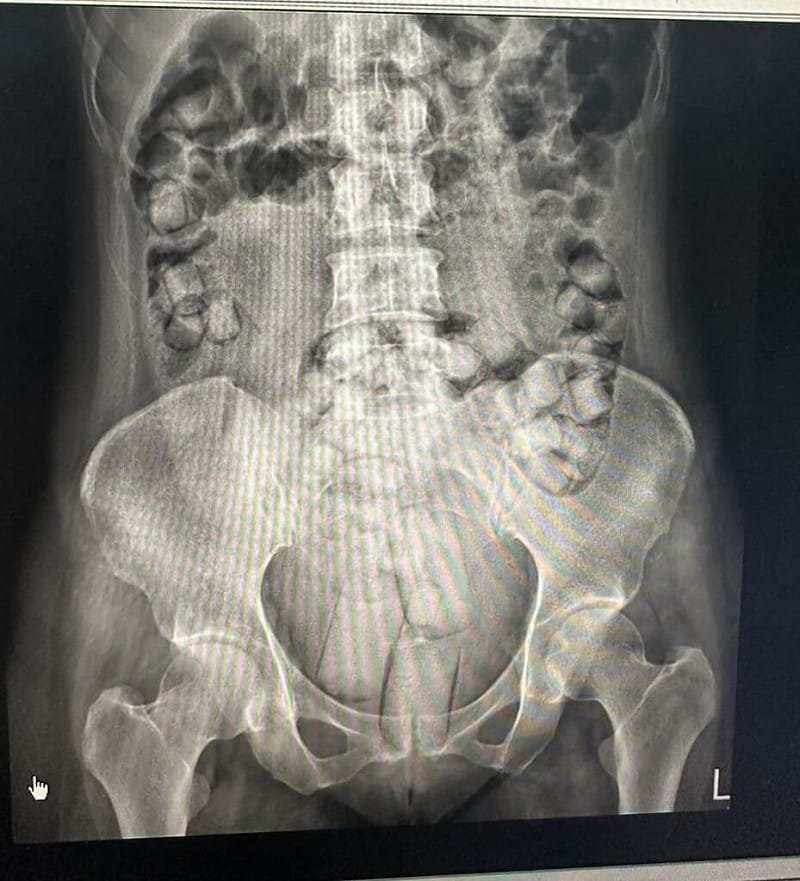

專案小組掌握2泰女的航班動態攔查毒品,2女被帶到高雄小港醫院排出毒品,2人分別吞食54顆、61顆海洛英毒品,共計664公克,市價約新台幣830萬元,約可供2萬5000人吸食。

海巡署偵防分署台中查緝隊9月在高雄小港機場查獲2名泰國籍女子,吞食海洛英毒品以人體夾帶方式走私,後到醫院排出多達115顆毒品膠囊。(民眾提供)中央社記者趙麗妍傳真 114年12月11日